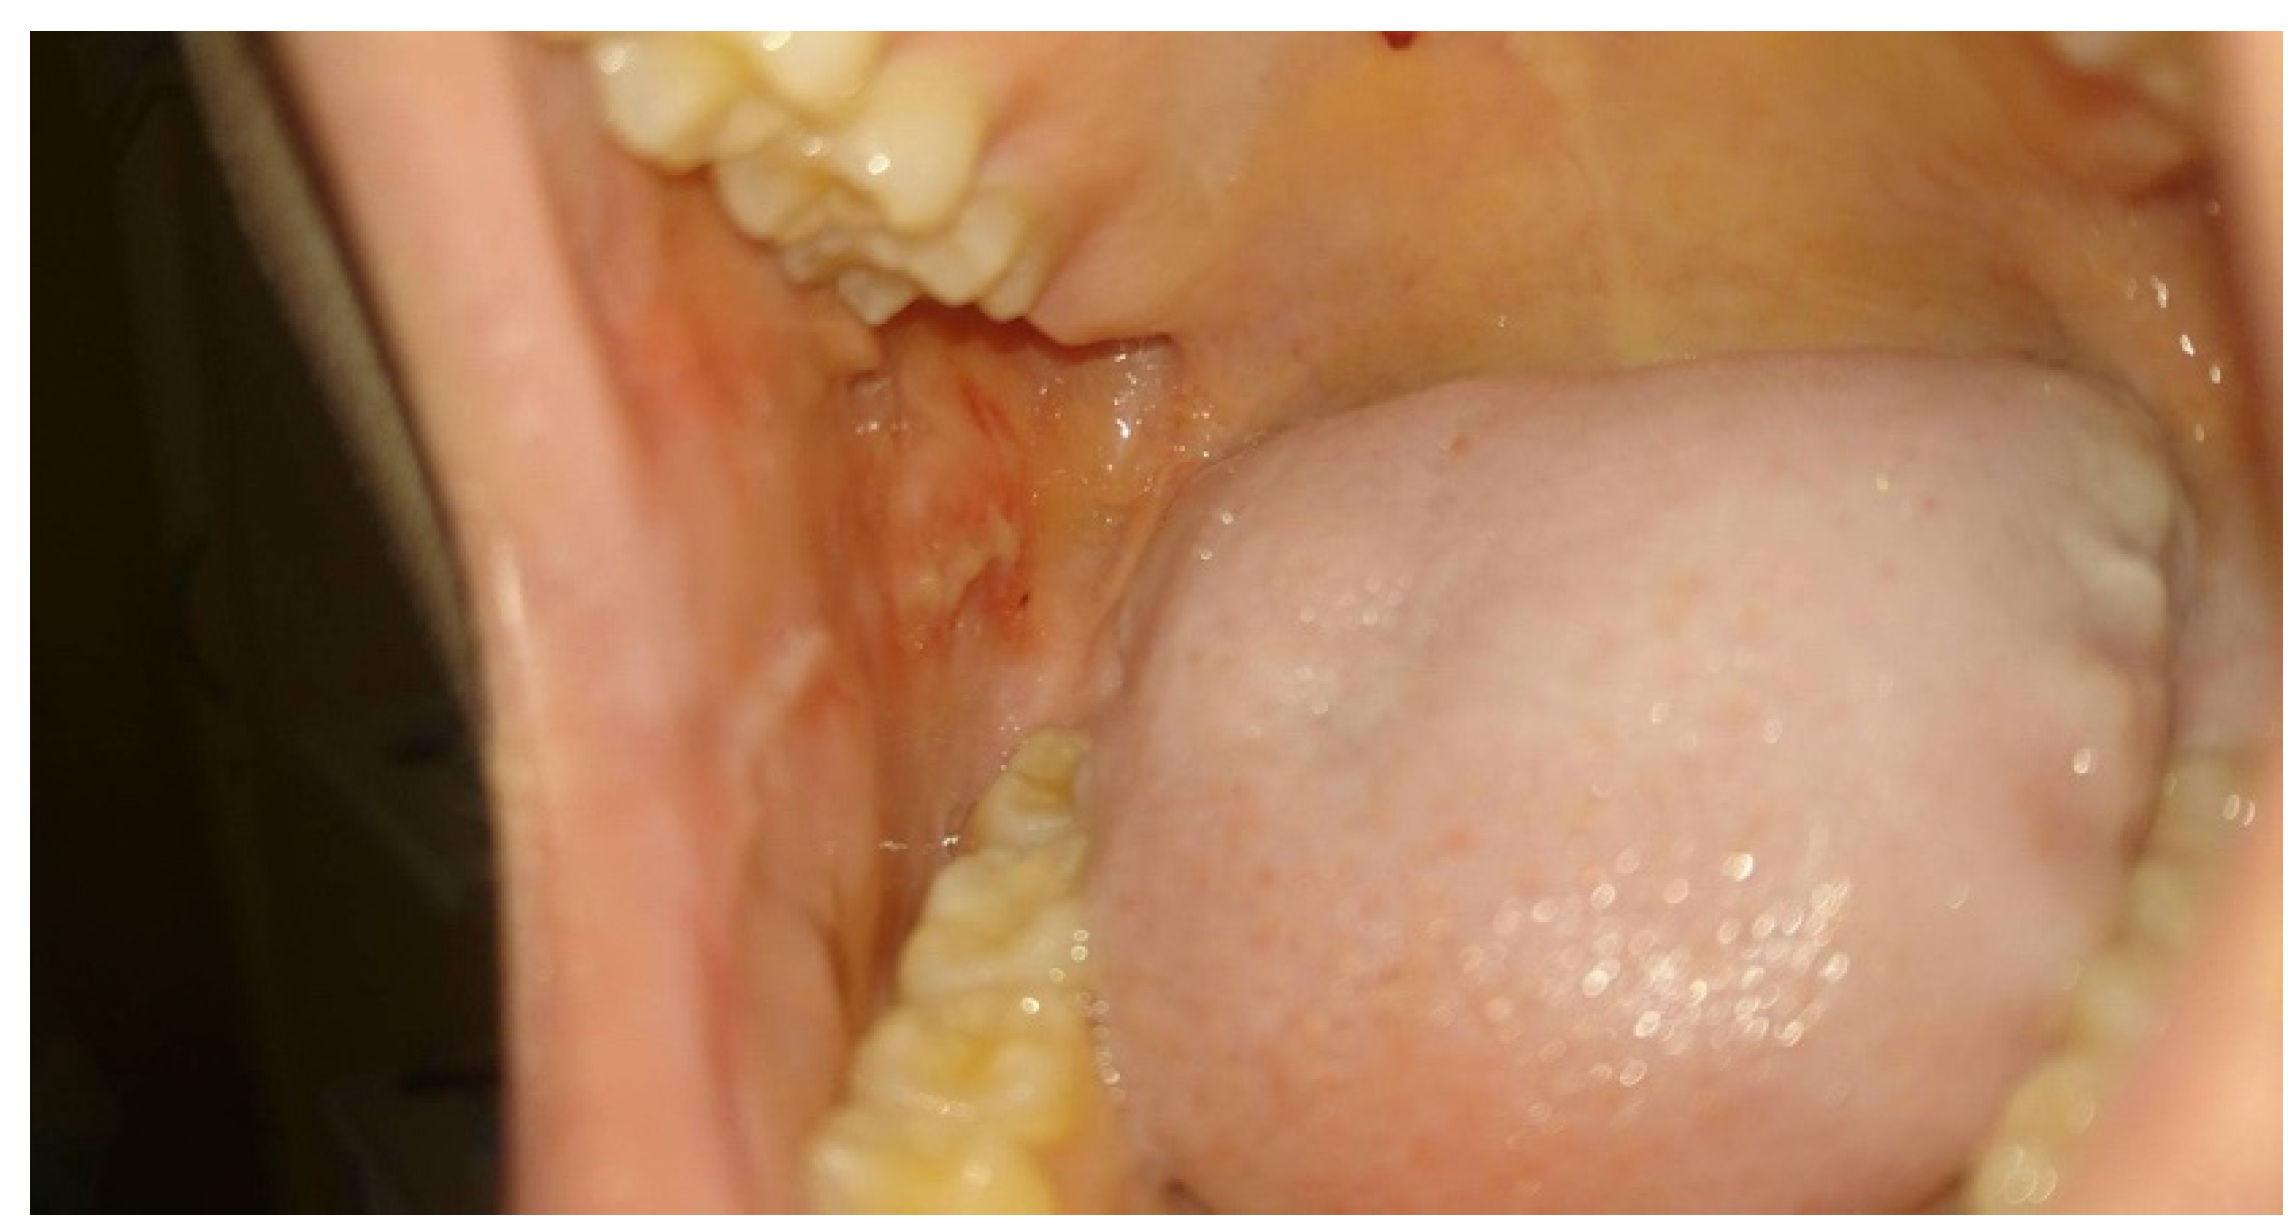

Moreover, a dependence between the state of the mucous membrane and peripheral blood parameters was observed. When there was a suppressed white cell count, the first symptoms of inflammation of the oral mucosa began to appear. However, parents, as well as experienced physicians and nurses, reported faster wound healing and better function of patients associated with PBM sessions even in cases of stagnated neutropenia or a significant decrease in the neutrophil count occurring during the OM episodes as presented in Figure 1 and Figure 2.

Figure 1. Intraoral photograph showing buccal mucosa with oral mucositis grade 3 (WHO scale) in a 15 year old girl, one week after methotrexate therapy, before PBM sessions, with a neutrophil count of 0.36 × 109/L. The patient was not able to eat solid foods, only liquids, with a pain level at VAS = 8.

Figure 2. The same patient after two PBM sessions (96 h later) with OM grade 1 (WHO scale), a neutrophil level of 0.43 × 109/L, and pain at VAS = 3, eating solid food.